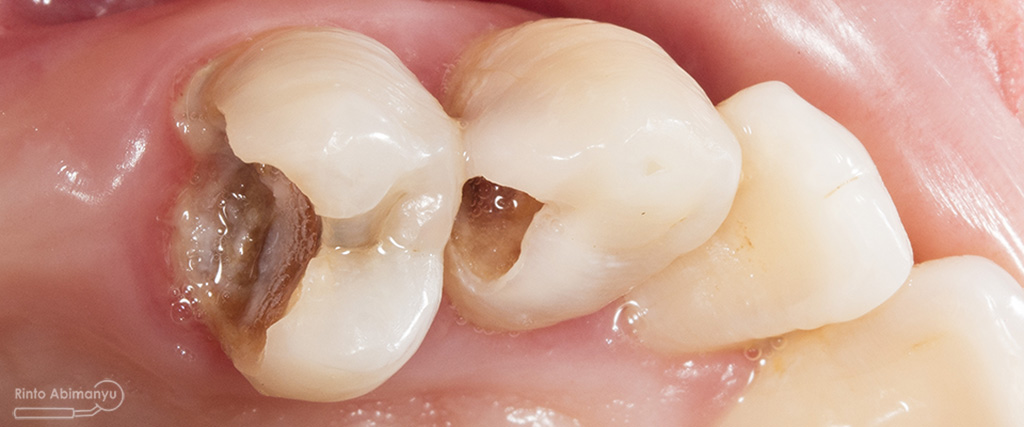

Kasus hari ini ceritanya datang seorang pasien wanita usia sekitar 50 an mengeluhkan gigi2 atas kirinya sering terselip makanan dan terkadang terasa senut-senut…

Pada pemeriksaan intra oral terlihat gigi 23 dan 24 mengalami karies dan cukup banyak sisa makanan terjebak disana…

Pemeriksaan respon dingin pun menunjukkan hasil negatif, untuk menambah data dalam penegakan diagnosis maka dilakukan pengambilan ronsen pada gigi2 tersebut